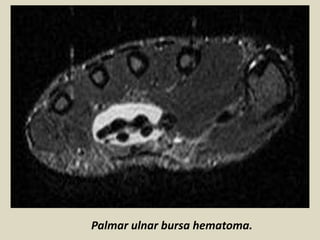

Palmar Bursae of the Wrist and Hand

Bursae are fluid-filled sacs lined by a synovial membrane, acting to decrease friction

between adjacent structures, allowing smooth, gliding movement. They are located

throughout the body in locations where tendons are closely apposed to bones and

rigid fibrous structures. The flexor tendons of the carpal tunnel are enveloped in two

palmar bursae: the ulnar bursa and the radial bursa. The ulnar and radial bursae

begin proximal to the carpal tunnel, usually near the distal margin of the pronator

quadratus muscle, and they extend distally to the level of the mid-palm, allowing for

longitudinal excursion of the tendons during normal wrist movement. These bursae

extend over a longer distance than the extensor tendon sheaths, a difference likely

related to the greater range of wrist motion that takes place in flexion compared with

extension The smaller radial bursa surrounds the flexor pollicis longus tendon. The

larger ulnar bursa surrounds the eight flexor digitorum tendons, doing so by means of

three invaginations: a deep invagination between the carpal bones and the profundus

tendons, a middle invagination between the profundus and superficialis tendons, and

a superficial invagination between the superficialis tendons and the flexor

retinaculum. These invaginations arise from a common space at the ulnar side of the

tendons adjacent to the FD5 tendon (7a). Although there are several anatomic

variations in the communication patterns between the ulnar bursa, the radial bursa,

and the digital flexor tendon sheaths, a typical anatomic arrangement found in the

majority of persons has been established through anatomic dissection as well as

tenography in cadavers.

Palmar ulnar bursa hematoma.

Palmar ulnar bursitis.